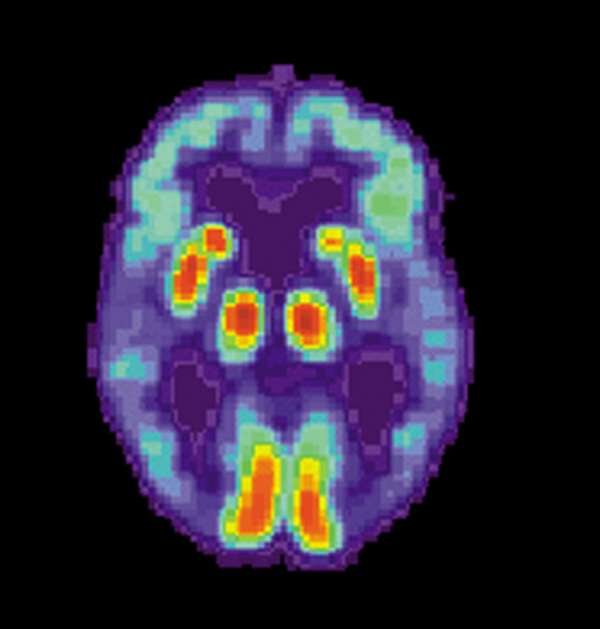

New study suggests sonic waves could help Alzheimer's patients regain memories

Researchers working with mice found that stimulating their forebrains with blasts of sonic waves helped get rid of protein buildup, a process that might one day be able to help people with Alzheimer's disease.

The study, published Wednesday in the journal Science Translation Medicine, showed that mice who had been bred to develop Alzheimer's did better on memory and navigational tests after having several ultrasound "treatments" compared to their counterparts that did not have any treatments, the Los Angeles Times reports. The researchers saw that after the mice received the scanning ultrasound, specialized immune cells in the brain called microglia were activated, and they swept up and disposed of excess amyloid.

Human trials are still a long way away, but researchers are excited about a non-invasive treatment that doesn't require drugs or surgery.